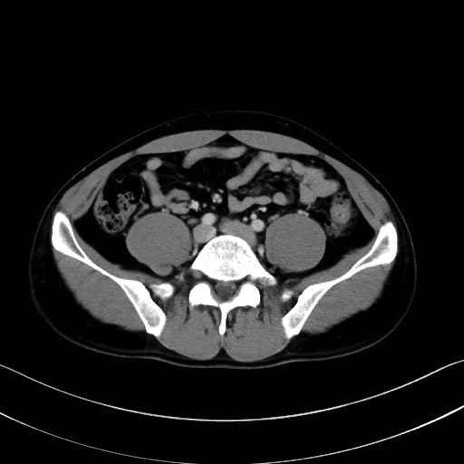

2. 腸腰筋群と骨盤底筋

大腰筋 (Psoas major)

腸骨筋 (Iliacus)

肛門挙筋 (Levator ani)